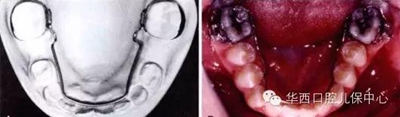

圖為下頜乳磨牙早失,未行間隙管理,繼承恒牙無法萌出(黃圈內(nèi))